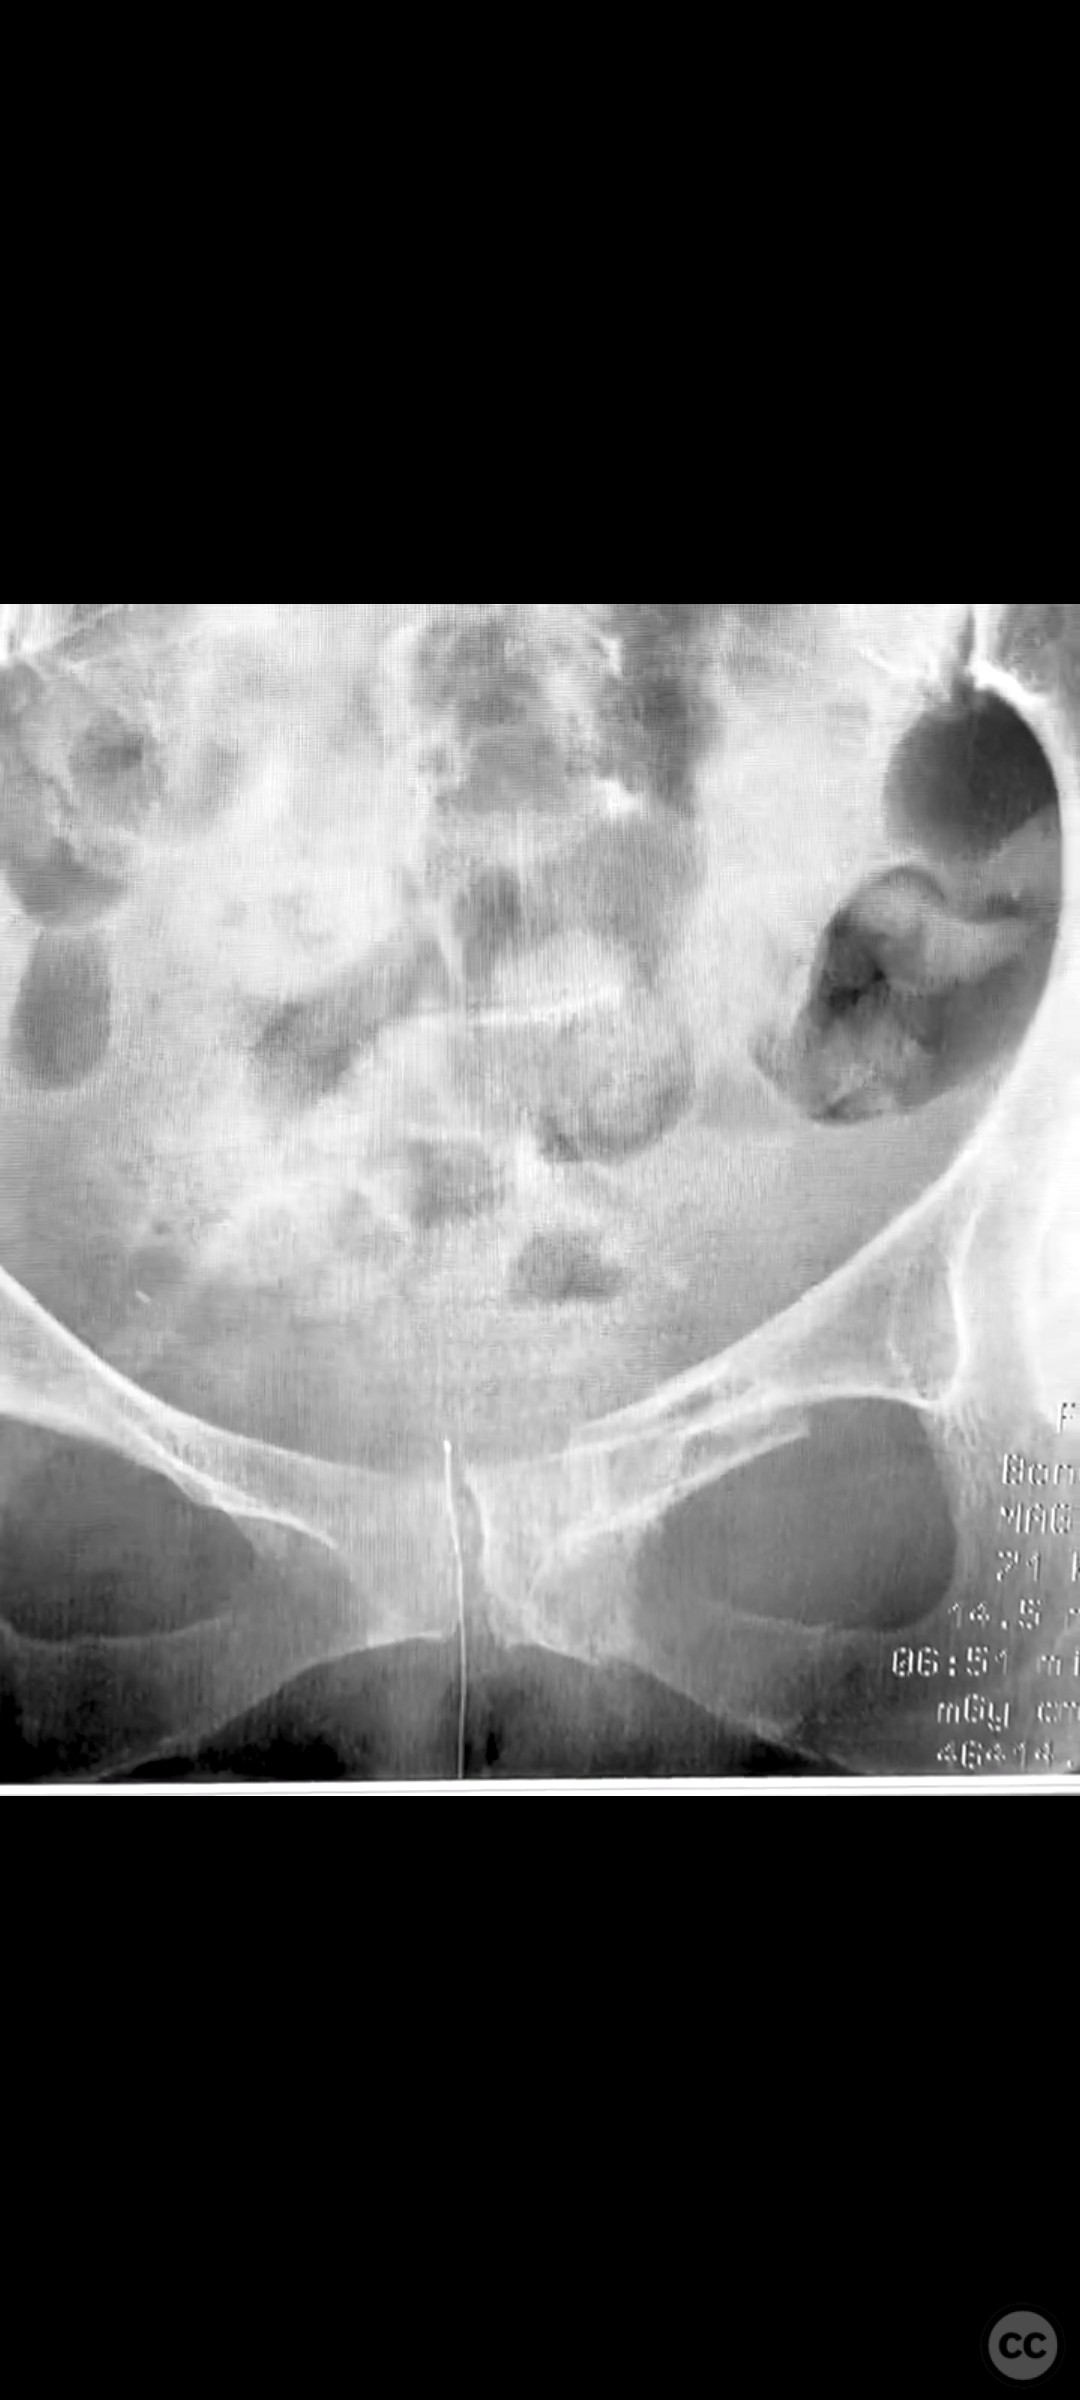

Pelvic Ring - AO/OTA 61x

Pelvis - AO/OTA 6x